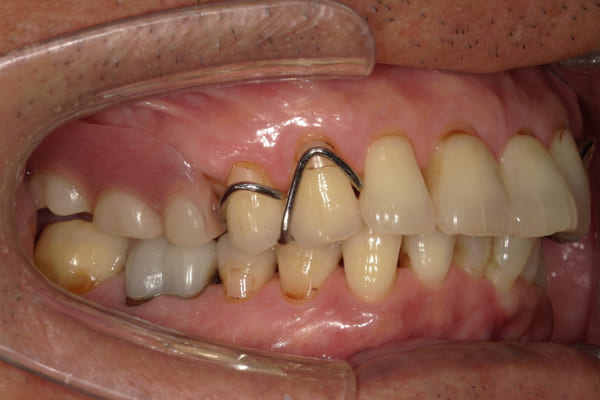

症例レポート[CASE.06]

- 男性(70代)

- 下歯がぐらぐらで抜けそうで痛い、何でも咬めるようにしてほしい

- 治療

- 上顎精密金属床部分入れ歯

- 下顎精密金属床部分入れ歯

- 陶材焼付鋳造冠 4歯

- 磁性アタッチメント 1歯

- 治療期間

-

- 上顎精密金属部分入れ歯:55万円

- 下顎精密金属部分入れ歯:77万円

(治療用義歯含、咬合平面等修正) - 陶材焼付鋳造冠:16.5万円×3歯

(ミリング加工) - 陶材焼付鋳造冠:14.3万円×1歯

(ミリングなし) - 磁性アタッチメント:11万円×1歯

(白金加金)

合計:157.3万円(税込)

奥歯がなくなり放置されていたため、前歯に負担がかかり、歯周病も併発されており歯がぐらぐらでお痛みも伴う状態でした。

可能な限り残せる歯は保存し虫歯治療を行い、どうしても残せないお痛みの歯のみ抜歯を行いました。

陶材焼着付鋳造冠 ミリングラべット加工

残りの歯が少ない場合は、入れ歯が動きやすく、またご自身の歯にも負担がかかるため、残りの歯の被せ物、入れ歯ともに、歯に負担がかかることを最小限にした特殊な加工を行い、歯を長持ちさせる設計としました。

上の入れ歯

下の入れ歯

上の入れ歯は、治療用入れ歯において、前方に違和感を訴えられていたため、違和感のない範囲を治療用入れ歯で決定し、最後の入れ歯に反映することで、上下ともに初めての入れ歯でしたが、違和感を感じることなくご使用になられることが可能になりました。

このように、お一人おひとり、お口の中の感覚は個人差が非常に大きいため、治療用の入れ歯でかみ合わせ、見た目、違和感、お痛みなど、あらゆる項目をチェックし、ご意見をお伺いし、ご相談のうえ最終的な入れ歯の設計を行い作製することで、その方に合った入れ歯が出来上がります。

治療後に入れ歯を外した上顎

治療後に入れ歯を装着した上顎

治療後に入れ歯を外した下顎

治療後に入れ歯を装着した下顎